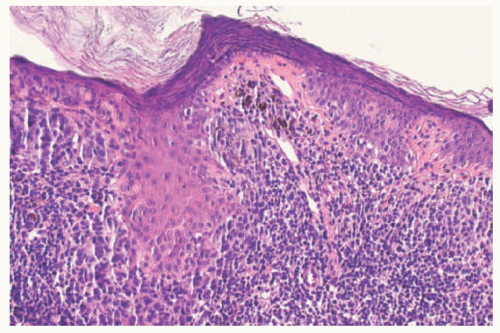

Compound nevus has a papulonodular appearance and may be flesh colored or pigmented depending in part upon the degree of pigmentation of the junctional component and/or pigmentary incontinence (Figure 22-4). A dense lymphocytic infiltrate may obscure the nevus cells throughout and may be accompanied by a clinical halo (Figure 22-5). Multiple halo nevi can be seen in association

with Turner syndrome. The number of junctional nests can be quite variable from case to case but seem to diminish with the age of the child at the time of biopsy/excision (Figure 22-6A & B). The dermal component may retain its nested pattern or acquires a more diffuse pattern as individual nevus cells, which trickle through the dermis and convey the impression that the cells are smaller with depth in the dermis compared to those nevus cells at or beneath the dermoepidermal junction; this phenomenon is referred to correctly or incorrectly as so-called maturation or senescence with depth (Figure 22-7). Among the junctional and superficial DN cells, the nuclei are larger with an open chromatin pattern and a micronucleolus and with depth into the dermis, the nevus cells are smaller including the nucleus with its more dense chromatin. Those nevi whose nuclei do not undergo this transition and whose nucleoli persist within the depths should be evaluated carefully and if need be shared with colleagues.

FIGURE 22-5. Compound melanocytic nevus from the posterior shoulder of a 14-year-old male showing a dense lymphocytic infiltrate obscuring in part the junctional and dermal nevus cells. This “halo” phenomenon is not always accompanied by a clinical halo.